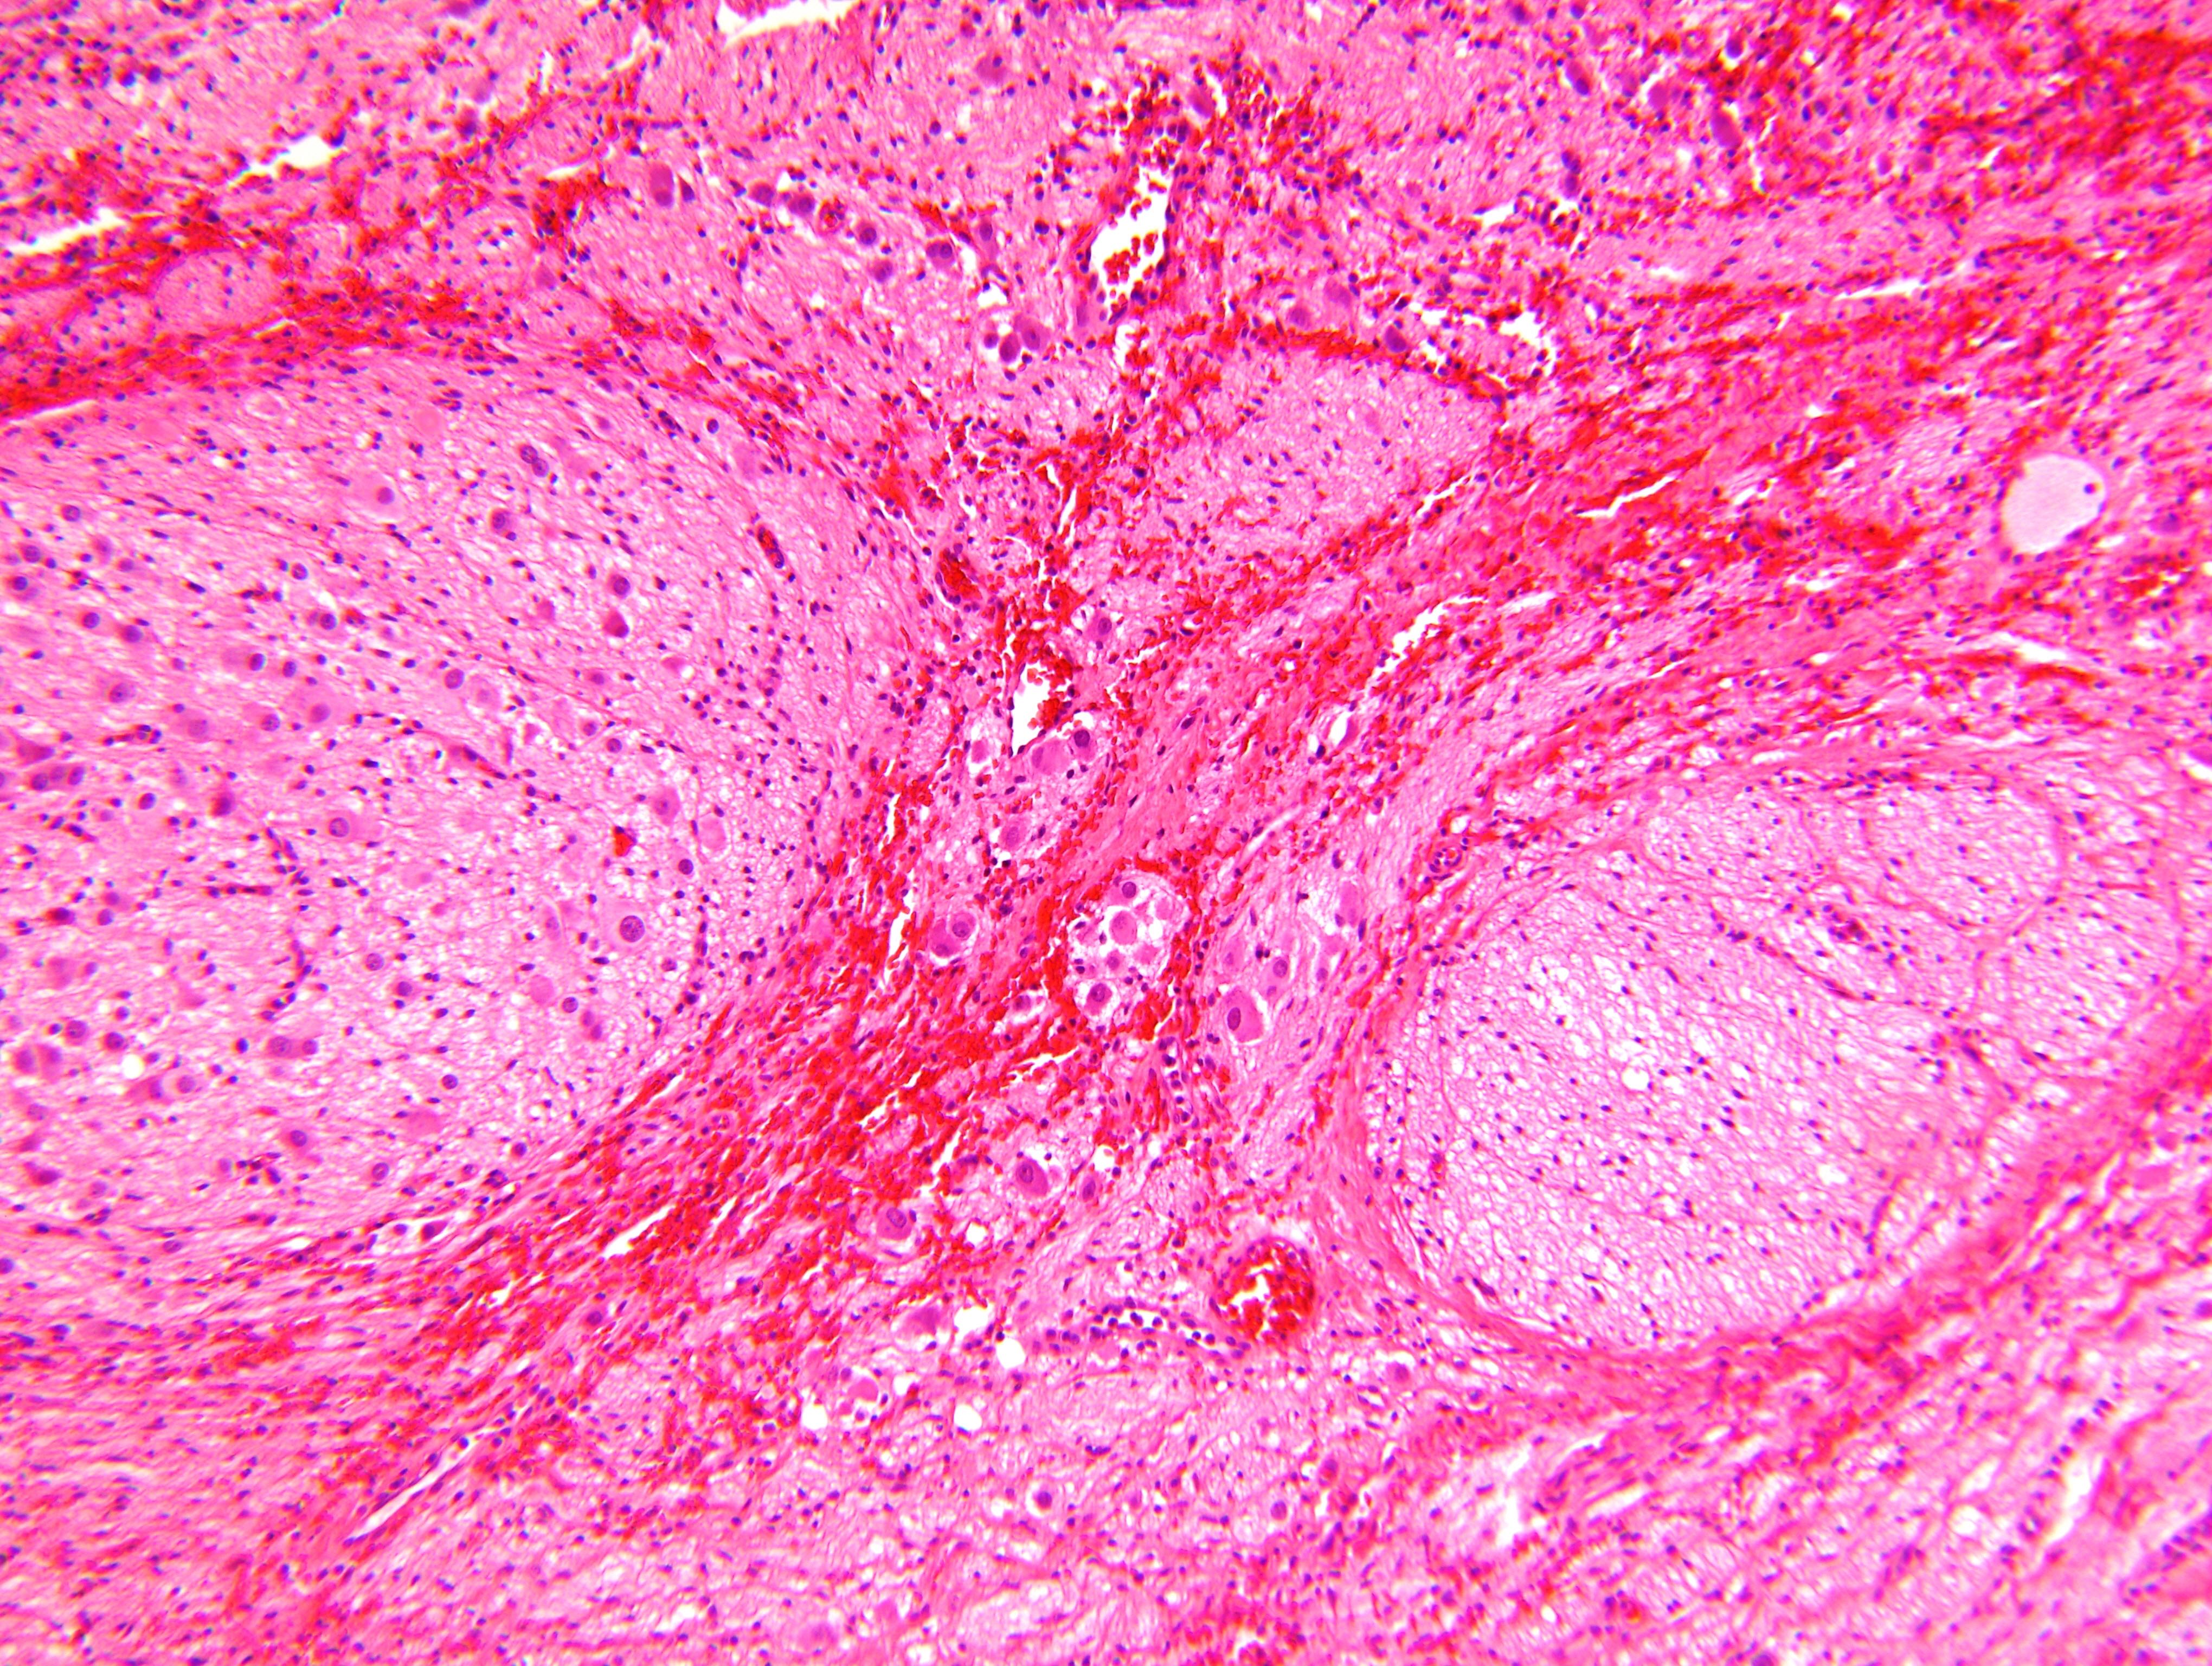

Microscopic (histologic) description

- Architecture: lobular, diffuse / solid, organoid

- Ganglion cells

- Abundant granular eosinophilic cytoplasm (Nissl substance = rough endoplasmic reticulum)

- Distinct cell borders

- Nuclear enlargement, eccentric nuclei, prominent nucleoli

- May see neuromelanin pigment (brown, finely granular; rarely present), cystic degeneration, hemorrhage, dystrophic calcification

Microscopic (histologic) images

Contributed by Carmen Perrino, M.D. and Debra L. Zynger, M.D.

Nodular type